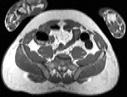

Visible Human male: Sectio transversalis 1777

CT

NMR

Pd                          / T2 \                         T1